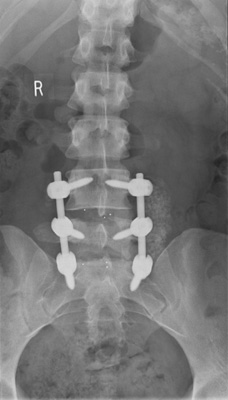

Following the discography findings I had (in layman’s terms), my lower two discs removed and a spinal fusion carried out on 15th October 2010. Otherwise known as a ‘two level spinal decompression and interbody fusion.’

Finally I thought I was getting somewhere and for a short time after the major surgery I appeared to be doing well. This was confirmed by the post op X-Rays. My thoughts started to move towards the excitement of going back to work, regaining my independence and getting my life back on track. However six weeks post op I began experiencing pain once more in my back and down the right leg, at this point I had no flexibility at all in my back and this continued despite regular Physiotherapy, doing exercises in the pool, and walking everyday twice a day as part of the recovery programme. After everything I’d been through, it all seemed as though it had been in vain and the initial optimism post op was now a distant memory……just feelings of hopelessness, loneliness and despair prevailed despite a loving family, great friends and my faithful cat Milly (although some friends drifted away as time went on and no recovery insight). I felt totally useless, a complete burden on everyone and quite frankly an emotional basket case! I found night times to be the worst, as they seemed so long and I couldn’t sleep for the pain. I was lucky if I got a couple of hours sleep so it wasn’t long before the effects of sleep deprivation kicked in, and I found myself turning into a person I hardly recognised anymore, so irritable and angry.